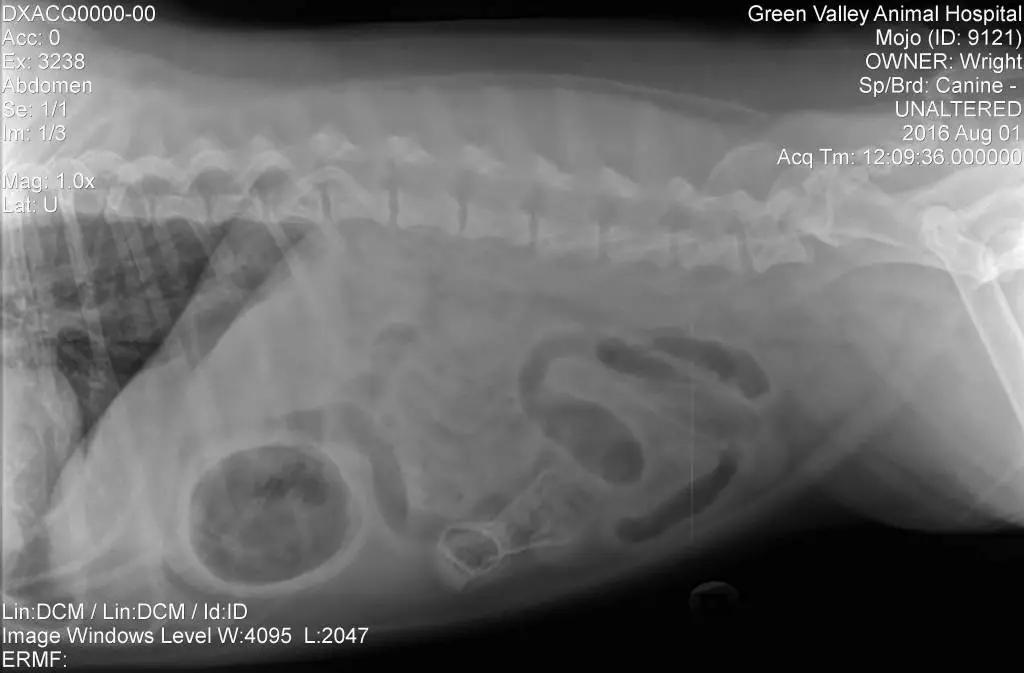

在兽医杂志《Veterinary Practice News》上有一个特殊的比赛,叫“They Ate What”,会评选出最匪夷所思的X光照。你能想象出家里那只活泼可爱的猫咪都会将些什么东西吃进肚肚吗?

这一年年的异食照片比赛真的很是让人大开眼界,惊奇之余,更是为这些可怜的宠物们担忧。

当猫咪吃下这些无法消化的东西后,会造成肠胃堵塞,只能通过手术才能处理,如果一时大意,耽误了治疗,猫咪恐有性命之忧。